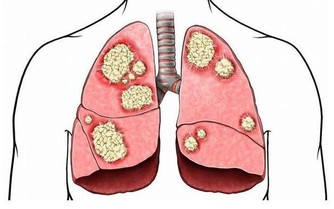

6、 豆腐渣樣白帶

豆腐渣樣白帶多與黴菌性陰道炎有關。黴菌性陰道炎是由假絲酵母菌感染引起常見的外陰陰道炎,其臨床表現為外陰陰道瘙癢、分泌物增多,白色稠厚,呈凝乳狀或者豆渣樣,外陰陰道瘙癢明顯,持續時間比較長,而且夜晚會更加明顯。部分患者可以出現外陰灼熱疼痛,性交、排尿痛等症狀。文章來源: https://wj.toutiao.com/q/125515/9R9jL421/6d22/#/